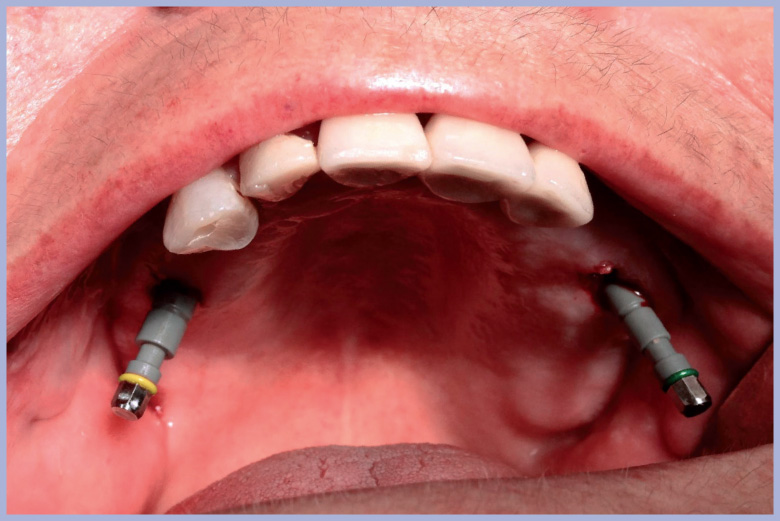

Dopo aver preparato i due siti distali con chirurgia flapless si inseriscono due impianti Max Stability lunghi 14 mm, uno di 3,75 mm e l’altro di 4,5 mm di diametro, inclinati (“tilted”) a 25°-30° (Fig. 3).

Successivamente si estraggono in maniera atraumatica i 5 denti residui e si posizionano altri due impianti Max Stability 3,75 x L 14 mm come impianti post-estrattivi nella posizione dei canini estratti (Fig. 4).

- Fig. 3 – Due impianti “tilted” Max Stability L 14 mm, uno Ø 3,75 e l’altro

- Fig. 4 – Impianti Max Stability in sede